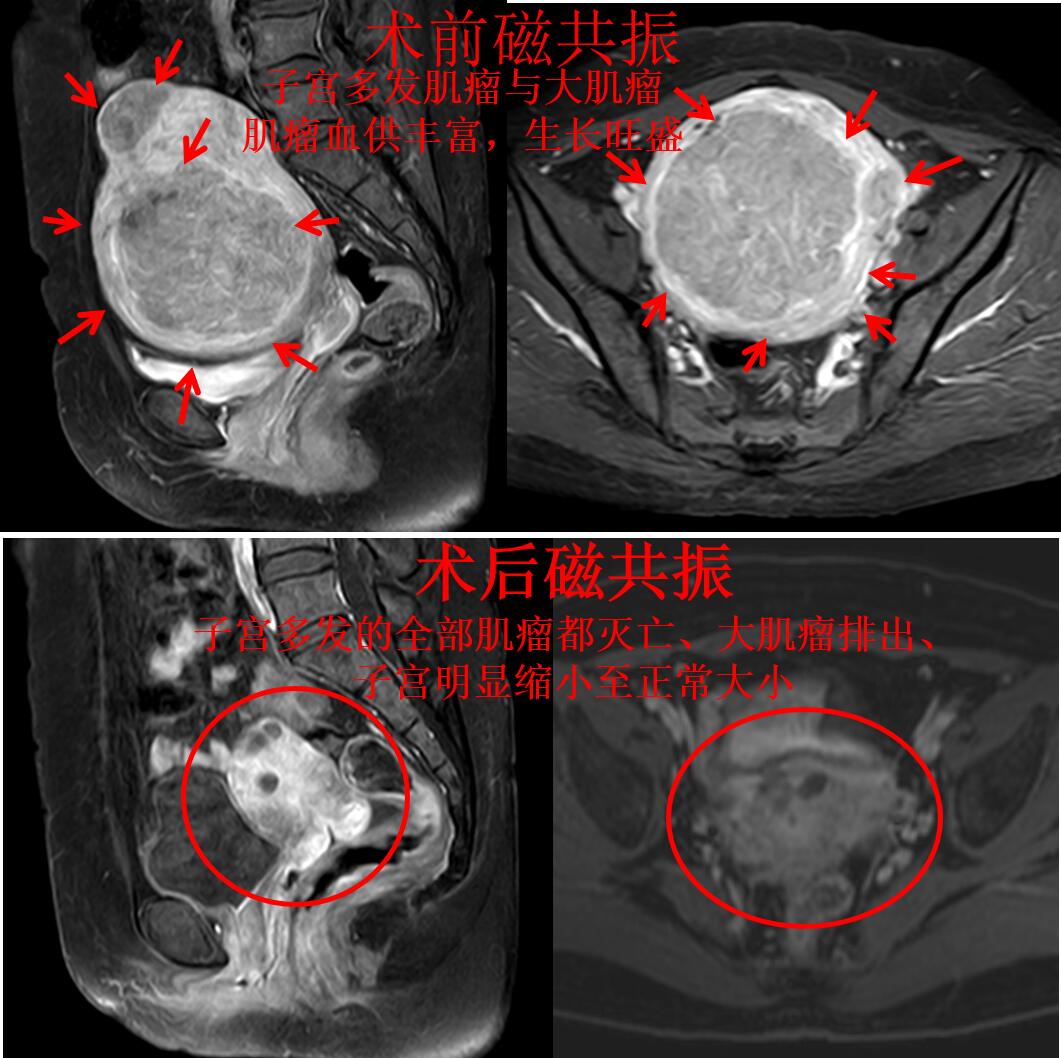

典型病例:乔女士今年45岁,月经量过多已经5年多了,还一个月比一个月厉害,在当地医院超声检查发现是多发子宫肌瘤在作怪。这半年来月经量超多,例假多的时候基本一个小时换一张,贫血53g/L,还到医院输血治疗,月经量超多,贫血严重,好不容易补血到80g/L,一来例假马上打回原形,重度贫血。在当地医院只有切除子宫的方法,乔女士不能接受子宫切除。门诊磁共振检查显示:子宫增大(136mm*101mm*109mm)、子宫多发肌瘤,最大肌瘤(106mm*95mm*89mm),如下图

随后乔女复查磁共振显示:子宫多发的全部肌瘤都灭亡、大肌瘤排出、子宫明显缩小了(如下图),真正的达到了一次打尽所有的肌瘤。